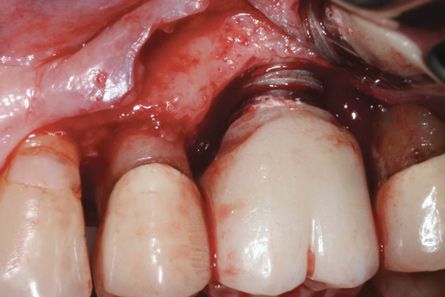

Some amount of microleakage can be expected with any current implant-abutment interface.23,24 External hexagon implants have been found to fail to prevent microleakage.23 Figure 3 and Figure 4 depict an external hexagon implant with an implant-abutment connection vulnerable to microleakage. This same study found internal hexagon implants with internal conical (Morse taper) connection to have the least amount of leakage. Zirconia abutments were found to have more microleakage than titanium abutments. As a result, this study recommended restricting the use of zirconia abutments to cases where esthetic demands are high.23

Fig 2. The height of this abutment was less than 2 mm on the facial. This may have led to additional marginal bone loss. Bacterial colonization of the abutment and the exposed implant body resulted in peri-implantitis.

Figure 2

Fig 3. Clinical and radiographic views of an external hexagon implant restored using a zirconia abutment. The radiograph indicates an implant–abutment connection vulnerable to microleakage. Severe bone loss was due to peri-implantitis.

Figure 3

Fig 4. Clinical and radiographic views of an external hexagon implant restored using a zirconia abutment. The radiograph indicates an implant–abutment connection vulnerable to microleakage. Severe bone loss was due to peri-implantitis.

Figure 4